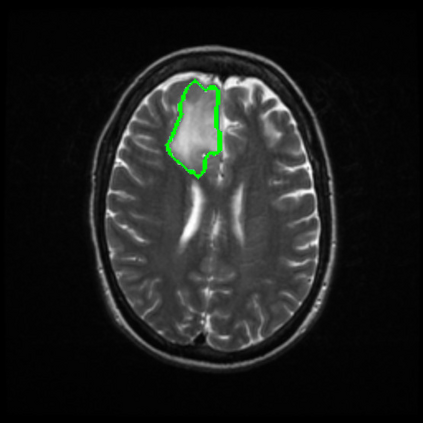

Radiomics uses quantitative medical imaging features to predict clinical outcomes. Currently, in a new clinical application, finding the optimal radiomics method out of the wide range of available options has to be done manually through a heuristic trial-and-error process. In this study we propose a framework for automatically optimizing the construction of radiomics workflows per application. To this end, we formulate radiomics as a modular workflow and include a large collection of common algorithms for each component. To optimize the workflow per application, we employ automated machine learning using a random search and ensembling. We evaluate our method in twelve different clinical applications, resulting in the following area under the curves: 1) liposarcoma (0.83); 2) desmoid-type fibromatosis (0.82); 3) primary liver tumors (0.80); 4) gastrointestinal stromal tumors (0.77); 5) colorectal liver metastases (0.61); 6) melanoma metastases (0.45); 7) hepatocellular carcinoma (0.75); 8) mesenteric fibrosis (0.80); 9) prostate cancer (0.72); 10) glioma (0.71); 11) Alzheimer's disease (0.87); and 12) head and neck cancer (0.84). We show that our framework has a competitive performance compared human experts, outperforms a radiomics baseline, and performs similar or superior to Bayesian optimization and more advanced ensemble approaches. Concluding, our method fully automatically optimizes the construction of radiomics workflows, thereby streamlining the search for radiomics biomarkers in new applications. To facilitate reproducibility and future research, we publicly release six datasets, the software implementation of our framework, and the code to reproduce this study.